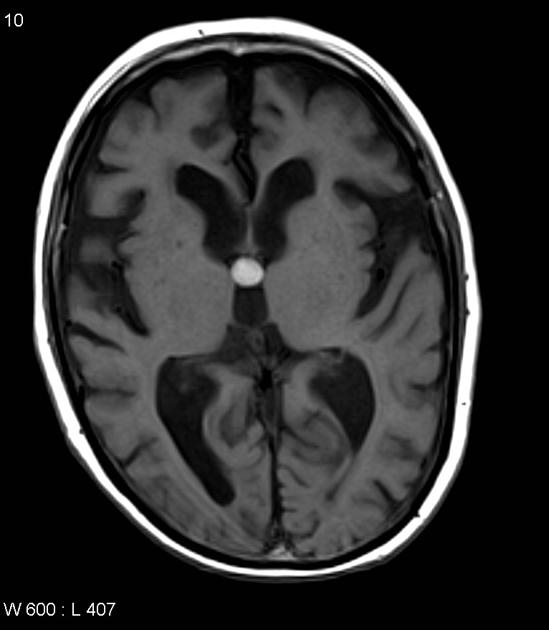

colloid cyst

benign but can cause acute hydrocephalus